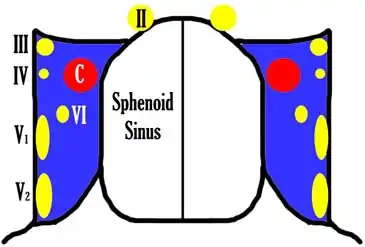

Sphenoid Sinus has 12 close structures: II, III, IV, V1, V2, VI, Vidian Nerve, Carotid artery, Brain, Dura, Pituitary.

Schematic of Cavernous Sinus Anatomy:

- II = Optic Nerve: 25-50% with bony dehiscence into sphenoid sinus.

- III = Occulomotor Nerve

- IV = Trochlear Nerve

- V1 = Ophthalmic division, Trigeminal Nerve

- V2 = Maxillary division, Trigeminal Nerve: exits foramen rotundum, superomedial to V3's foramen ovale.

- VI = Abducens Nerve

- C = Carotid Artery: often with bony dehiscence into sphenoid. Together with CN II forms opticocarotid recess.